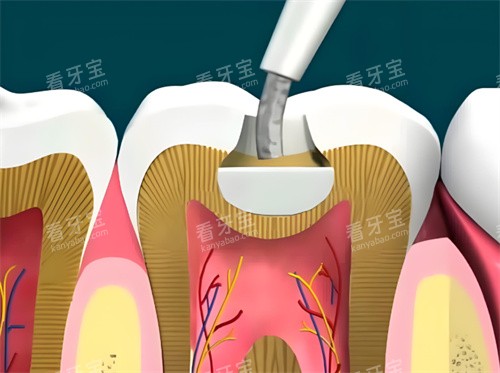

?嵌体修复:当牙齿缺损较大,无法直接用材料充填时,需要取模定制高嵌体或嵌体。材料多为瓷块或树脂块,强度高、更精密。此为“补牙升级版”,单颗价格通常在2000-5000元以上。

诊疗操作费

即医生的技术劳务费用,包括去腐、备洞、隔湿、填充、塑形、抛光等一系列精细操作。这部分费用在医院有明确的定价,私立医院则通常打包在总价中。